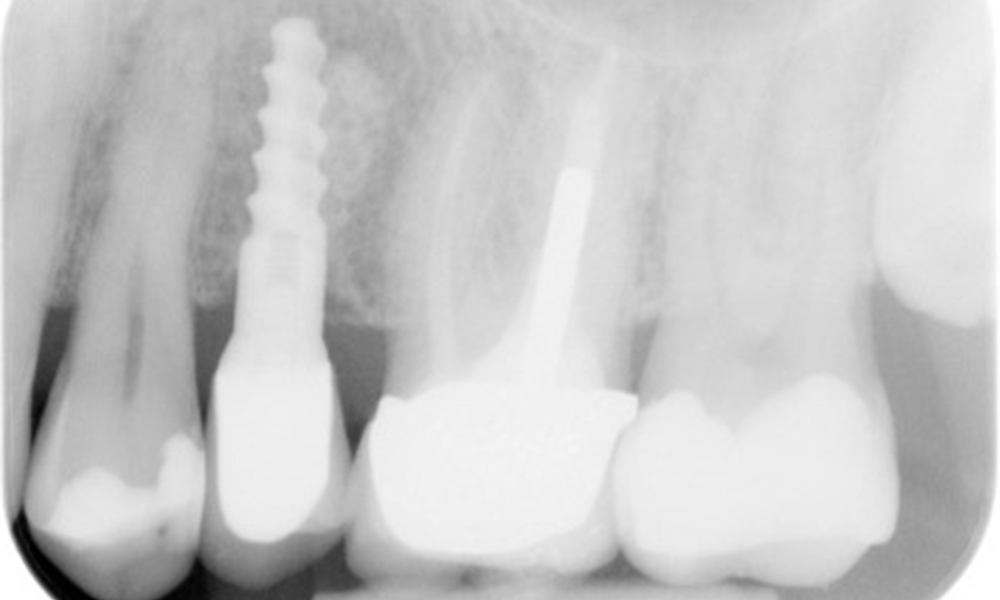

В медицинската история 55-годишният пациент заявява, че няма хронични заболявания и не приема никакви лекарства. Начинът на живот на пациента също е без забележки. Пациентът има няколко зъбни възстановявания и два импланта (2-ри и 4-ти квадрант). Въз основа на настоящите данни се установява гингивит при иначе стабилно пародонтално състояние върху редуцирания пародонт (стадий III, степен А).

Предишни лечения: зъбни възстановявания (съчетание от нескъпоценни метали и керамика), два импланта (2-ри, 4-ти квадрант)

Препоръчително лечение според IPC

Пациентът не показва особени рискови фактори със специфични дентални последици. Следователно ключовият фактор е изискването по отношение на оралното здраве. В това отношение доброто орално здраве се проявява при стабилен, редуциран пародонт. Ако при контролен преглед се установят данни за увеличаване на дълбочината при сондиране в сравнение с изходното ниво, съчетано с дифузно кървене, следва да се предприеме диагностика с помощта на рентгенова снимка (дентален рентген), за да се установи загуба на периимплантатна кост на ранен етап и да се предприемат съответните интервенции.